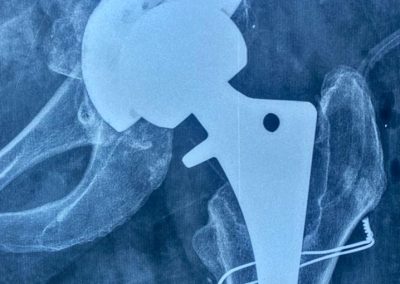

أجرت جراحة نصف مفصل بالحوض منذ ٢٠٠٦

تبين الأشعات وجود فجوات عظمية بالحق مع بروز داخلي لرأس المفصل مع وجود الام شديده.